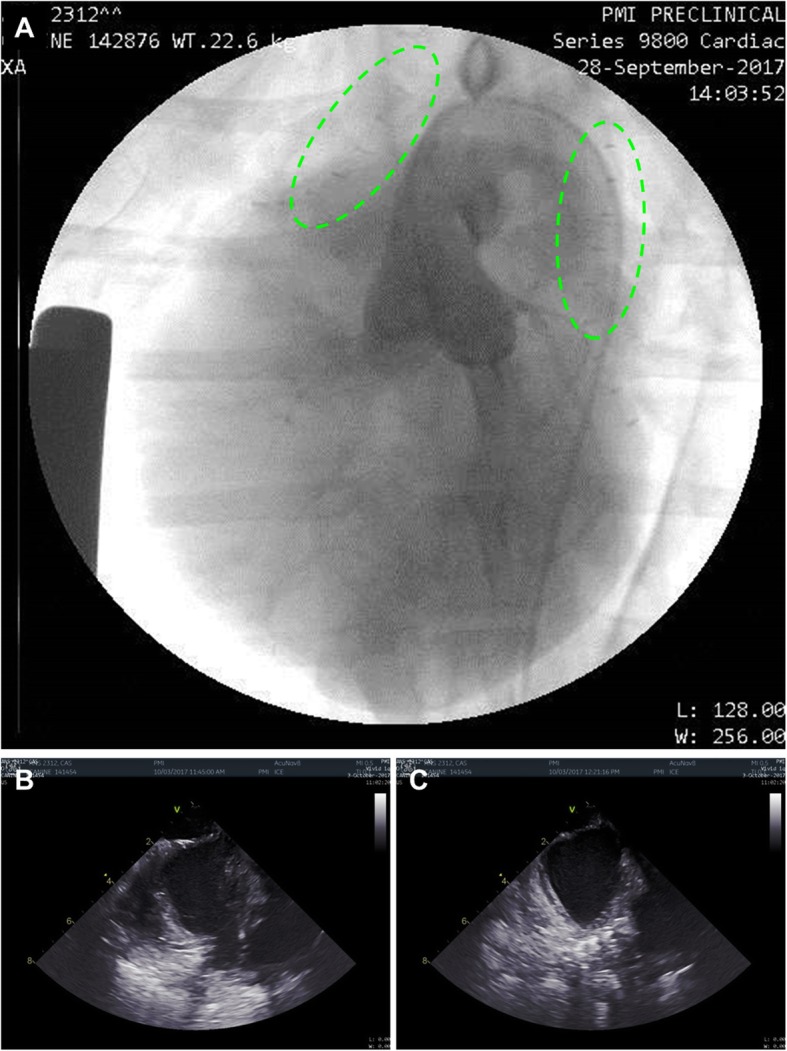

Fig. 5.

a-c Post-deployment endocardial assessment. Left-coronary angiography demonstrating patent coronary arteries with two fasteners deployed on the LAA and RAA (green dotted lines) (a). Intra-cardiac echo showing the LA and the open LAA pre-deployment (b) and the occluded LAA post-deployment of the fastener (c)

No evidence of tissue damage or bleeding was detected on endocardial evaluation. Angiography displayed an unchanged left coronary system. In 8/9 animals, ICE assessment of the LAA showed complete LAAO without any evidence of fluid communication (Fig. 5a-c). Complete LAAO could not be confirmed in the ninth animal, but was subsequently confirmed in necropsy, indicating a good efficacy profile of the device (100%).